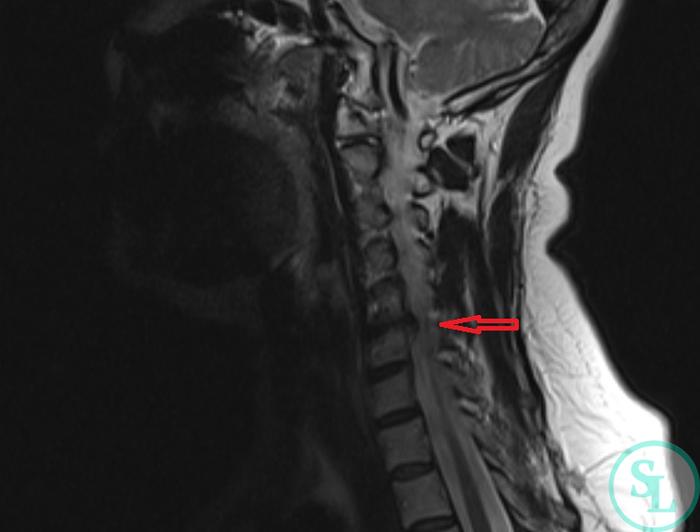

Для диагностики грыжи межпозвонкового диска C5-С6 врач может назначить магнитно-резонансную томографию (МРТ), которая позволяет получить детализированное изображение и оценить состояние межпозвонковых дисков и окружающих тканей. Ранняя диагностика и терапия помогут избежать развития более серьезных осложнений.

Согласно рассказам пациентки и данным медицинской документации, боли в области шеи беспокоят её уже довольно долго. Постепенно они стали хроническими, и не поддаются облегчению с помощью ненаркотических противовоспалительных средств (НПВС). Консервативное лечение не дало результата. В 2022 году было проведено МРТ шейного отдела позвоночника, которое показало дегенеративные изменения. Выявлена грыжа межпозвонкового диска на уровне C5-C6 с образованием стеноза и сильным сжатием нервных структур.